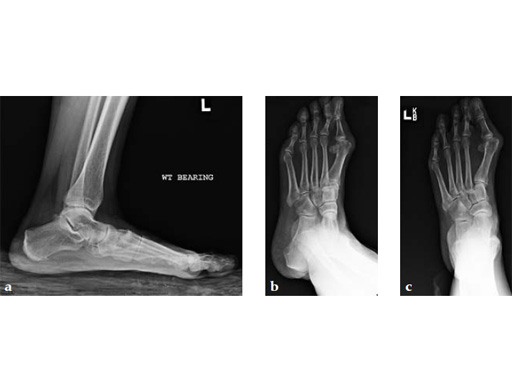

A 60-year-old woman with pes plano abductovalgus (flatfoot deformity).

Case provided by Andrew Sands, New York, New York, USA

The patient was treated by headless compression screw 6.5 tuber osteotomy, TMT plantarflexing osteotomy, and first TMT fusion a plate.